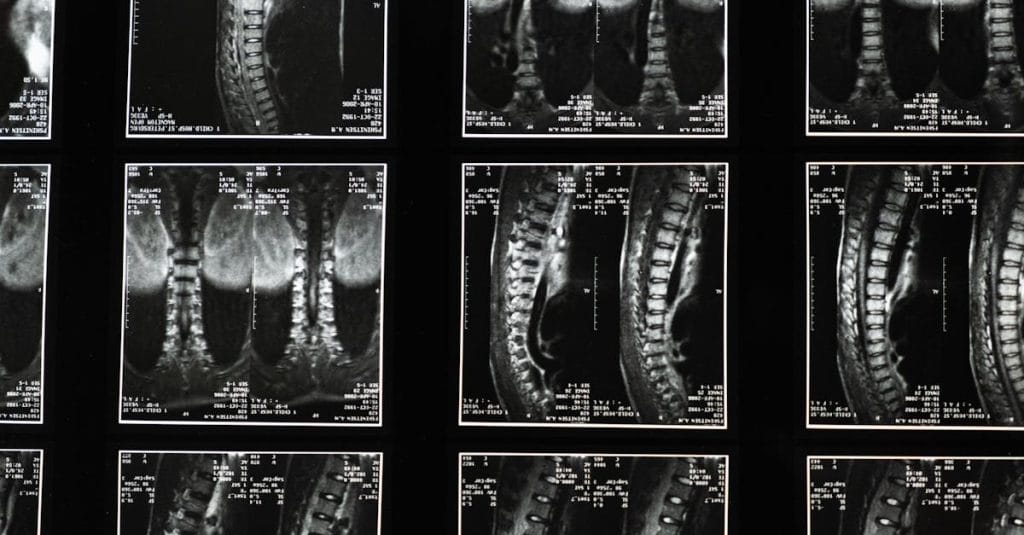

Quels examens permettent de diagnostiquer la sciatique?

Une IRM ou une radiographie est généralement nécessaire pour confirmer la cause de la sciatique.